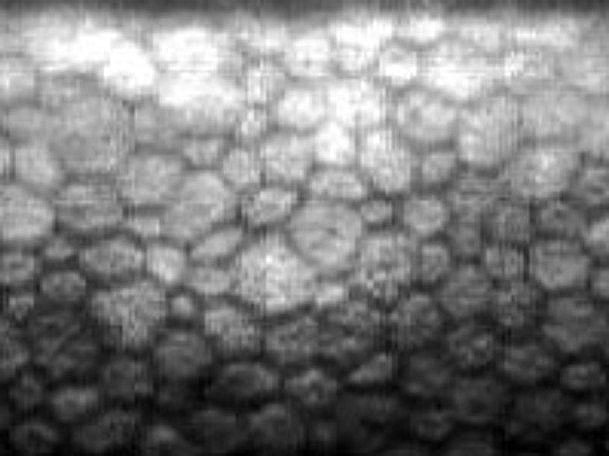

酸素を通しにくいコンタクトレンズを長時間使うと、角膜が酸素不足になり、感染症を起こしたり、角膜の透明性を保つ内皮細胞が減って視力に影響が出ることがあります。

※角膜内皮細胞は一度壊れると再生しません。損傷がひどいと、将来的に白内障の手術が受けられなくなる場合もあります。

細胞の一部が死滅し、それを埋めるために細胞が肥大・変形しています。(角膜内皮細胞解析装置による画像)